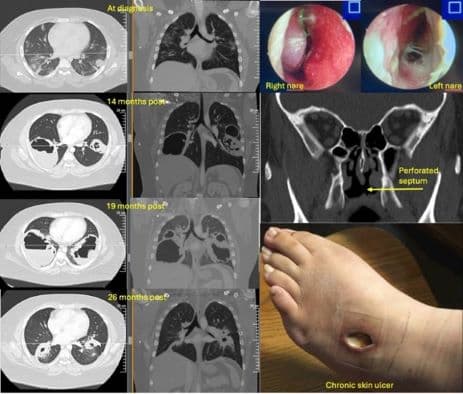

The ACR seeks images representing a diverse range of patients that show either educational or remarkable manifestations of the rheumatic disease in the following category: